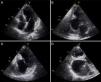

O ecocardiograma transtorácico revelou a presença de pseudoaneurisma/aneurisma ventricular inferior e posterior gigante, preenchido parcialmente por trombo, e condicionando deformação significativa da geometria ventricular (Figura 1; Vídeo 1‐4). Apesar das suas grandes dimensões, o aparelho subvalvular mitral encontrava‐se íntegro, não existindo regurgitação. Dada a dúvida no diagnóstico diferencial, foi realizada ressonância magnética cardíaca que confirmou tratar‐se de aneurisma ventricular gigante (maior eixo de 6,7cm) com trombo no seu interior (Figura 2; Vídeo 5‐6), pelo que iniciou terapêutica anticoagulante. A cintigrafia de perfusão miocárdica exclui isquemia e confirmou necrose do território inferior e posterior. O cateterismo cardíaco pré‐operatório revelou oclusão crónica do segmento proximal da artéria coronária direita e ausência de doença significativa no território coronário esquerdo. A ventriculografia demonstra o volumoso aneurisma ventricular (Figura 3; Vídeo 7). O doente foi submetido a correção cirúrgica do aneurisma: foi observado um volumoso aneurisma da face inferior do ventrículo esquerdo (Figura 4). Após entrada em circulação extracorporal foi feita aneurismectomia parcial com remoção de enorme trombo parietal e encerramento do colo do aneurisma com patch de Dacron® com 2×3cm (Figura 4). O ventrículo esquerdo foi encerrado com sutura contínua. O pós‐operatório decorreu sem intercorrências e o doente teve alta para o domicílio no 5.° dia de pós‐operatório.

Ecocardiograma transtorácico bidimensional: (A) Apical quatro câmaras, sem alterações; (B) apical duas câmaras a revelar aneurisma ventricular gigante da parede inferior com trombo no seu interior; (C) apical duas câmaras modificado, mostrando preservação do aparelho subvalvular mitral; (D) apical três câmaras modificado a demonstrar volumoso aneurisma ventricular na parede posterior com trombo no seu interior.